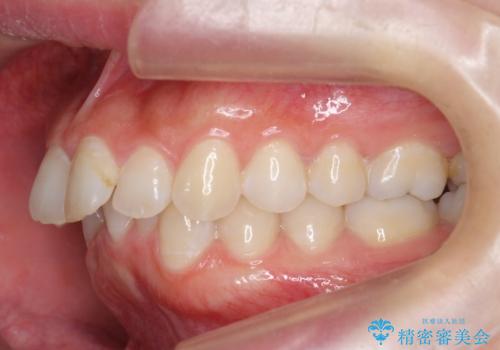

前歯をさげたい 歯を抜かずに マウスピース矯正で治したい

- 上の前歯が出ているとのことで来院。

歯を抜かずに、上の奥歯を後ろにさげつつ上の前歯を小さく少し削る処置を行い前歯の角度を修正しました。

右上下の奥歯もすれ違い咬合も、治療で改善しています。

下の前歯が生まれつき3本でしたので上下の正中は合わない仕上がりとなります。